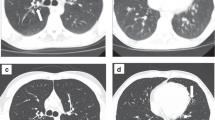

Exemplary in- and output of fully automated CT-based body composition analysis (BCA). (A) Visualization of feature extraction for BCA and marker aggregation. BCA network detects the different BCA features within the chest CT scan. Those raw features are combined with bone to calculate body size-adjusted biomarkers. The tissues are encoded in colors as follows: pink: bone, yellow: muscle, orange-brown: subcutaneous adipose tissue (SAT), purple: epicardial adipose tissue (EAT), light blue: paracardial adipose tissue (PAT) and turquoise: inter- and intramuscular adipose tissue (IMAT). (B) Exemplary chest CT in axial view before (left) and after (right) elexacaftor/tezacaftor/ivacaftor therapy showing decreasing bronchiectasis wall thickening and regredient mucus impaction. (C) Exemplary chest CT in axial view showing increased proportion of subcutaneous adipose tissue (SAT, orange-brown) and increased inter- and intramuscular adipose tissue (IMAT, turquoise) after elexacaftor/tezacaftor/ivacaftor therapy.